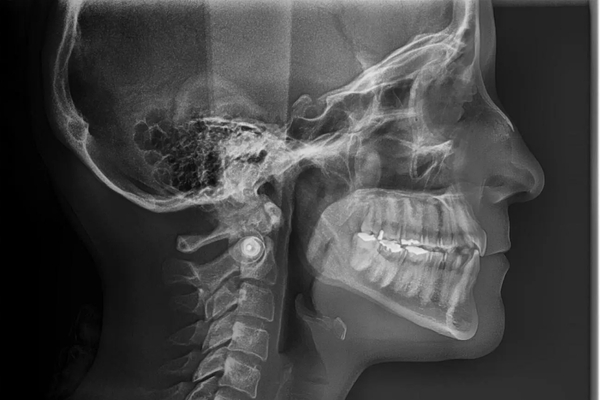

Radiografias

Extra Orais

As Radiografias Extra Orais englobam uma série de exames realizados com o filme ou sensor posicionado fora da boca. Além da Panorâmica, esta categoria inclui as Teleradiografias e outras incidências que avaliam a relação dos ossos da face e estruturas maiores. Elas são essenciais para estudos cefalométricos em ortodontia e para a análise das articulações temporomandibulares (ATM), sendo vitais para diagnósticos que vão além da arcada dentária.